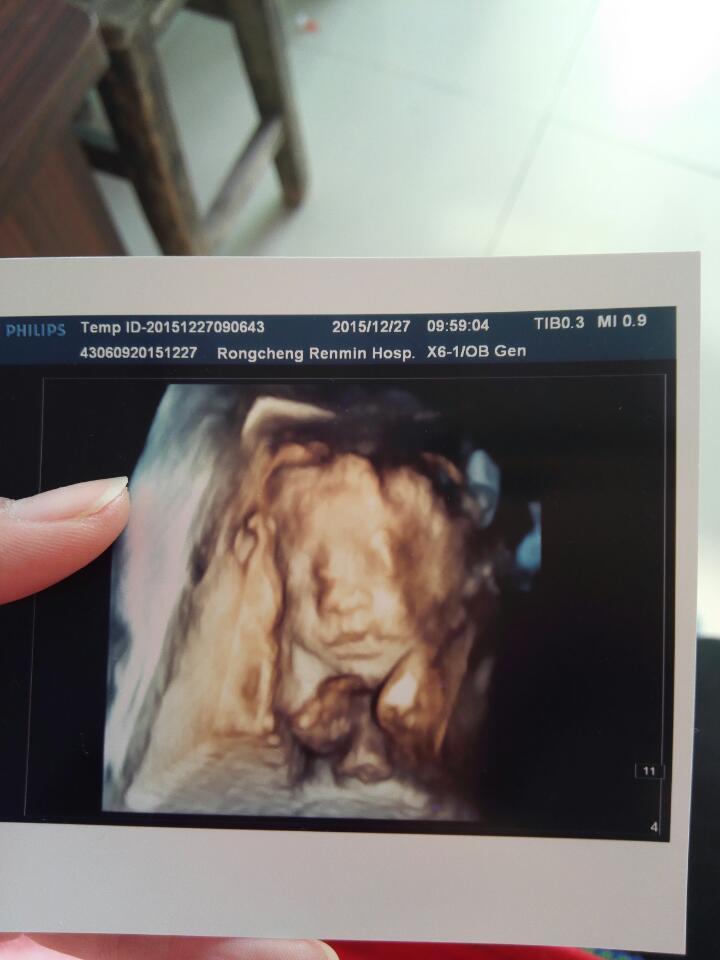

四维照片,就是眼睛有点模糊 四维照片,就是眼睛有点模糊 点击展开 伴你到白头_GmlP 2015-12-28 12:41 为您推荐: 其他回答 嗯嗯😄😄😄😄 自从有了你(宝宝) 2015-12-28 13:47 嗯现在不行了还有一个月就生了 自从有了你(宝宝) 2015-12-28 13:43 我也是啊…… 自从有了你(宝宝) 2015-12-28 13:40 我当时查的臀位 自从有了你(宝宝) 2015-12-28 13:14 嗯你这多少周做的啊 自从有了你(宝宝) 2015-12-28 13:14 加载更多 相关问题 做四维,宝宝照片是眼睛睁开的 正常吗 我怀孕5个半月了,做四维的时候我就看到孩子一只眼睛,那只好像� 医生为什么让我做三维,而不是四维,三维照不到宝宝的照片,有点失望